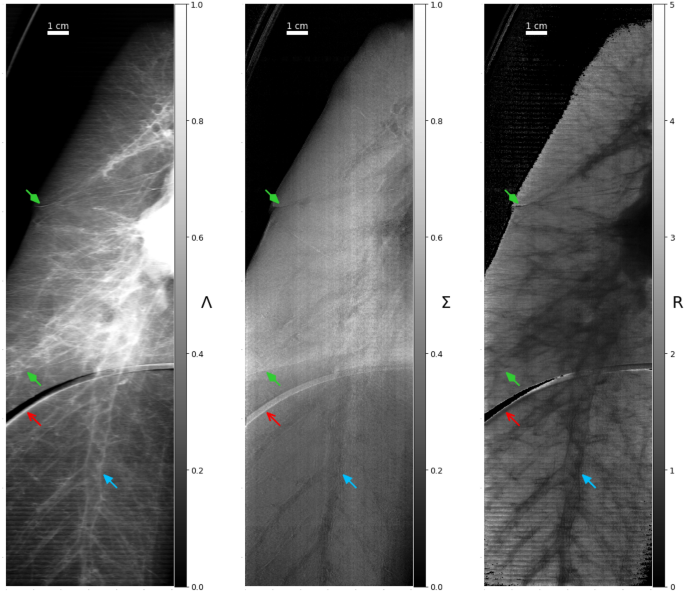

Stitched planar views of an inflated porcine lung at an autocorrelation length of 0.36 \({\upmu {\textrm{m}}}\). The images consist of 120 fields of view, each 2 mm tall (vertical) and acquired in 45 s with 15 phase steps, for a total acquisition time of 1.5 h. Left: The attenuation image was corrected for the container attenuation. Middle: The dark-field channel. Right: The R-value. The forked red arrows point to artifacts from the artificial diaphragm. The triangular blue arrows point out one of the visible bronchi. The green diamond head arrows highlight interfaces (lung fissures) between different lobes of the lung.

The results in Fig. 8 show R-values and trends with autocorrelation length for the PMMA micro-spheres and the lungs as were obtained in an earlier study on a polychromatic Talbot-Lau interferometer22. The lungs in this study induced a dark-field signal more closely resembling densely packed 200 \({\upmu {\textrm{m}}}\) diameter PMMA spheres compared to the previously reported values22. This is likely due to higher differential pressure between lung and ambient that caused the alveoli to expand more and leading to a lower dark-field signal. Also, the overall slope of the dark-field or R-value over the autocorrelation lengths (provided in Fig. 8) is larger compared to the study22, which can be attributed to visibility hardening46 that is manifest in the gradual reduction of the slope towards saturation under their polychromatic illumination. The radiographs in Fig. 9 show the added information provided by the dark-field. This includes signal generated by the alveoli, the measurement being sensitive to the mean structure size19,20,21, and could benefit the diagnosis of emphysema, fibrosis or similar diseases that alter the structure of the lung and are hence expected to change the dark-field signal47. The R-value of the radiography is constant for the lung tissue and drops for regions with large air vessels which have relatively thick and absorbing walls. This is also evidence for a uniformly inflated lung without noticeable tissue damage from slaughter process, freezing or disease. The artifact visible in the middle region of Fig. 9 (and Fig. S1) stems from the diaphragm underneath the lungs (visible in Fig. 2 on the middle image) which is not fixed to the outer shell of the phantom and is moved between the sample and reference measurements.